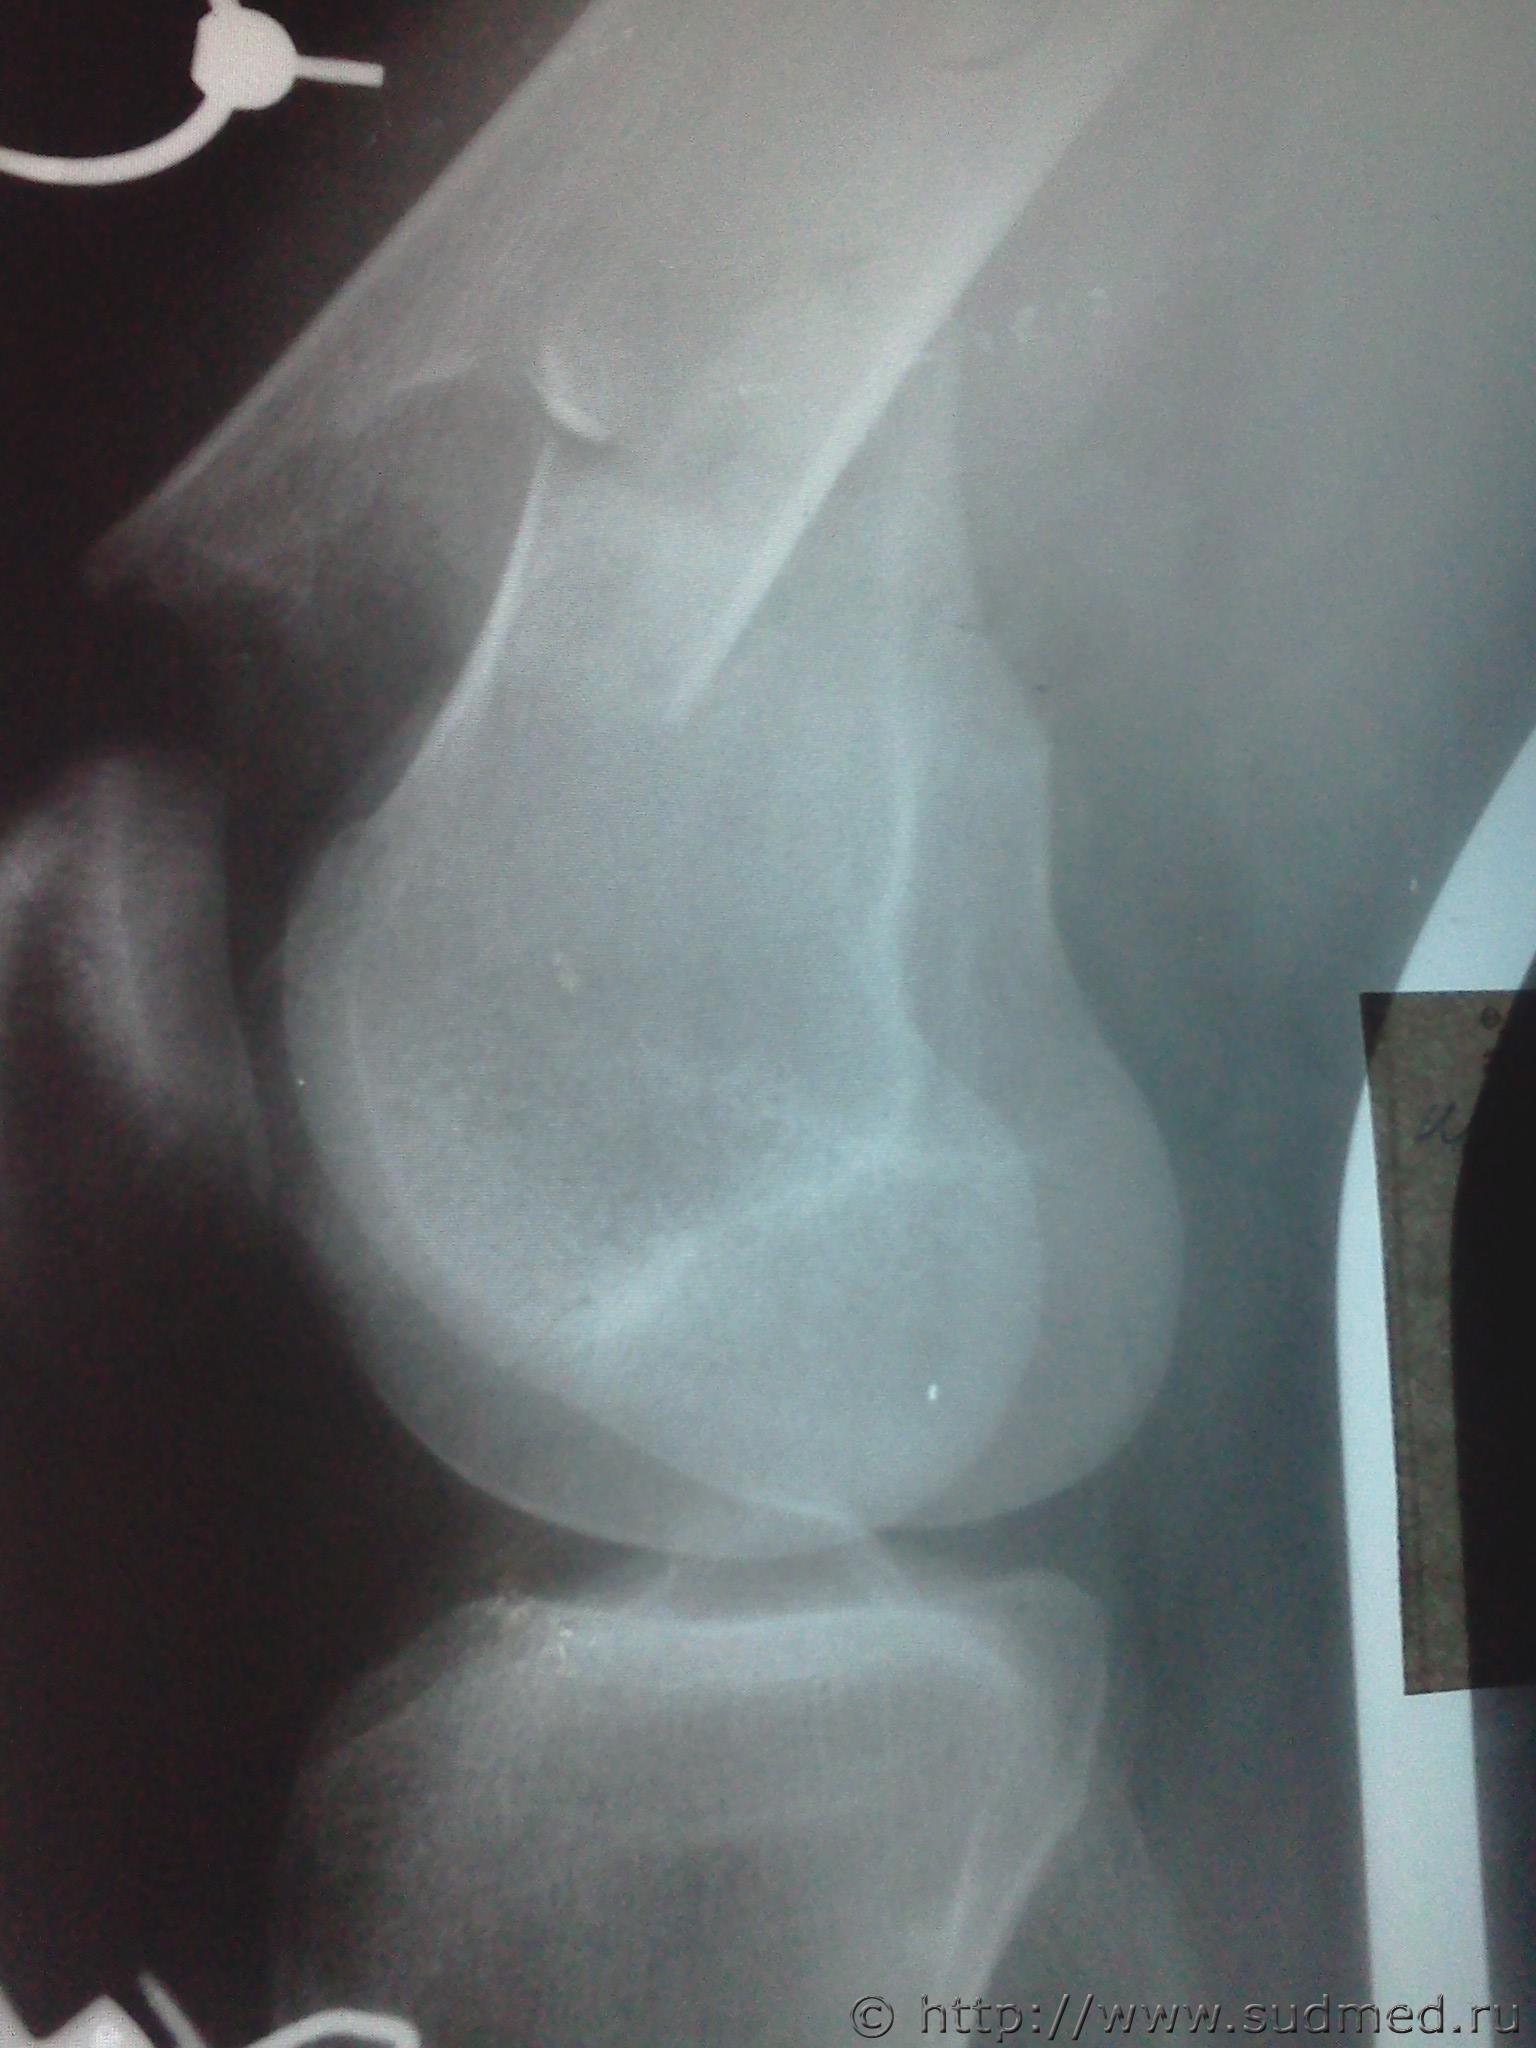

правая бедренная

левая большеберцовая

Эскизы прикрепленных изображений

Судебная медицина - Прикрепленное изображение Судебная медицина - Прикрепленное изображение Судебная медицина - Прикрепленное изображение Судебная медицина - Прикрепленное изображение

Я бы не задумываясь, отнес бы каждый перелом к тяжкому вреду.

Тяжкий вред здоровью - пп.

6.11.6. открытый или закрытый перелом диафиза бедренной кости; и

6.11.8. открытый или закрытый перелом диафиза большеберцовой кости;

Однозначно - тяжкий вред. Перелом диафиза в нижней трети.